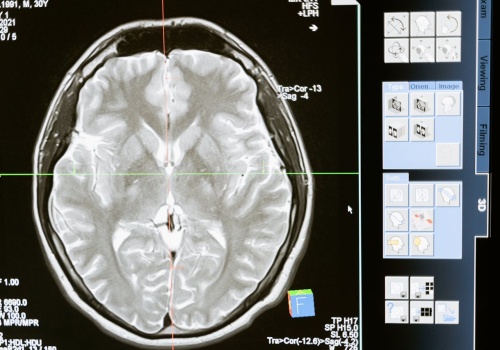

Miękki implant mózgowy 3D inspirowany origami może rozwiązać problem cofania się nici znany z klasycznych systemów BCI. Artykuł Nowy implant mózgowy inspirowany kirigami porusza się z mózgiem i zwiększa stabilność sygnału pochodzi z serwisu Alert Medyczny.